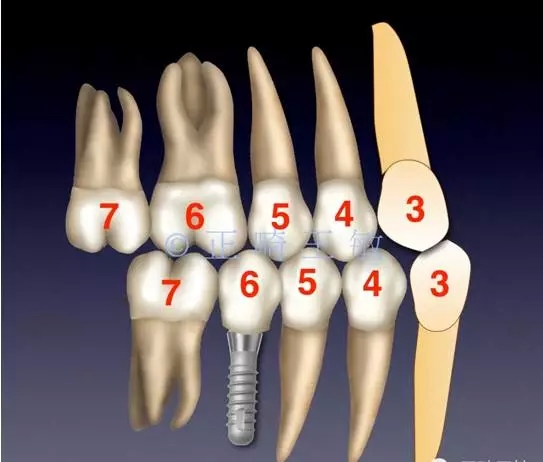

31.webp.jpg

首先我的想法是找到最不需要移動的牙齒,最穩(wěn)定的牙齒。發(fā)現尖牙的前后向關系還不錯,只是下頜還需要內收,而左側上5已經咬在下6的窩里,這樣的咬合關系已經很穩(wěn)定,左側拔掉一顆下牙就足以解決下牙的擁擠和咬合的問題。

32.webp.jpg

33.webp.jpg

然后來看看右側。

34.webp.jpg

也同樣,尖牙很穩(wěn)定。

35.webp.jpg

只是偏合,為了糾正,47的支抗不免喪失,最終會做成一個這樣的關系。

36.webp.jpg

這時,順理成章的種一個小一點的46,同樣是尖窩相對,同樣的穩(wěn)定。

34.webp (1).jpg